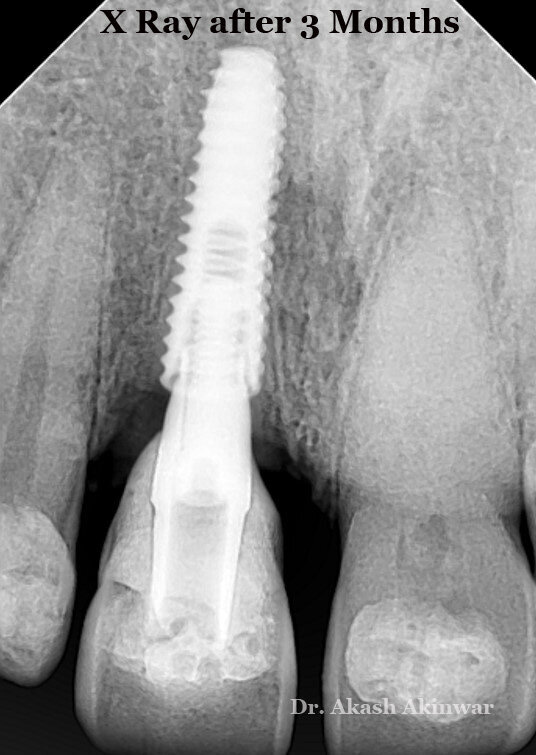

The patient was from another state, so he was kept under observation at 7 days, 1 month, 2-month intervals by another dentist at his native place and was recalled for final prosthesis after 3 months.

The patient reported 3 months later with the satisfactory hard & soft tissue healing. Implant level open tray impression was taken and the master cast was obtained. Next, using a castable abutment, a screw-retained PFM prosthesis was made.